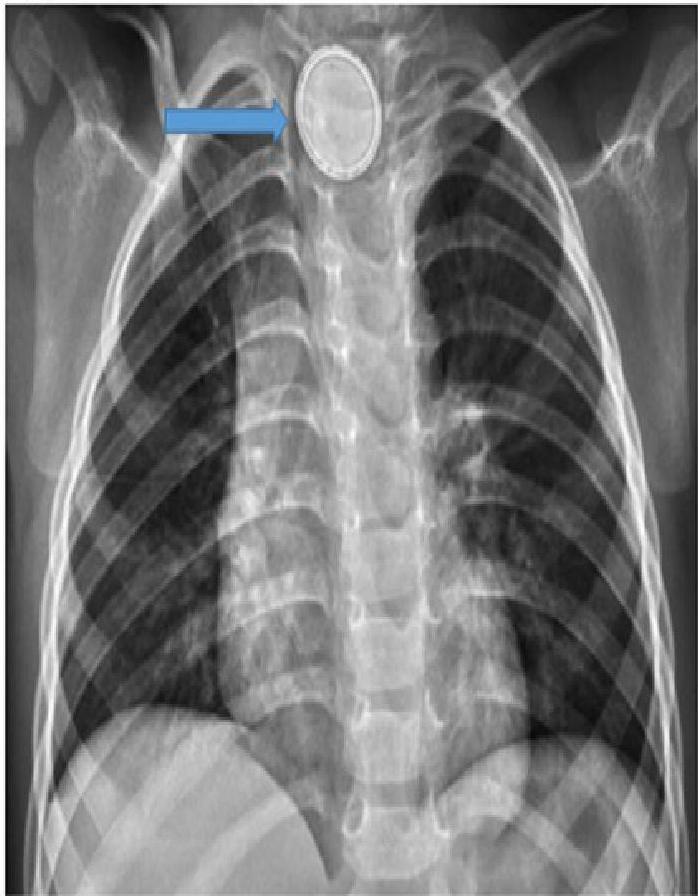

The “Button Battery” Emergency Risk

- Risks: Esophageal burns, fistula formation (tracheoesophageal), hemorrhage.

- X-Ray Sign: “Double Halo” or “Step-off” sign on lateral view.

- Action: Immediate removal required if stuck in the esophagus.

A, B, C: Imaging examples of button battery ingestion.